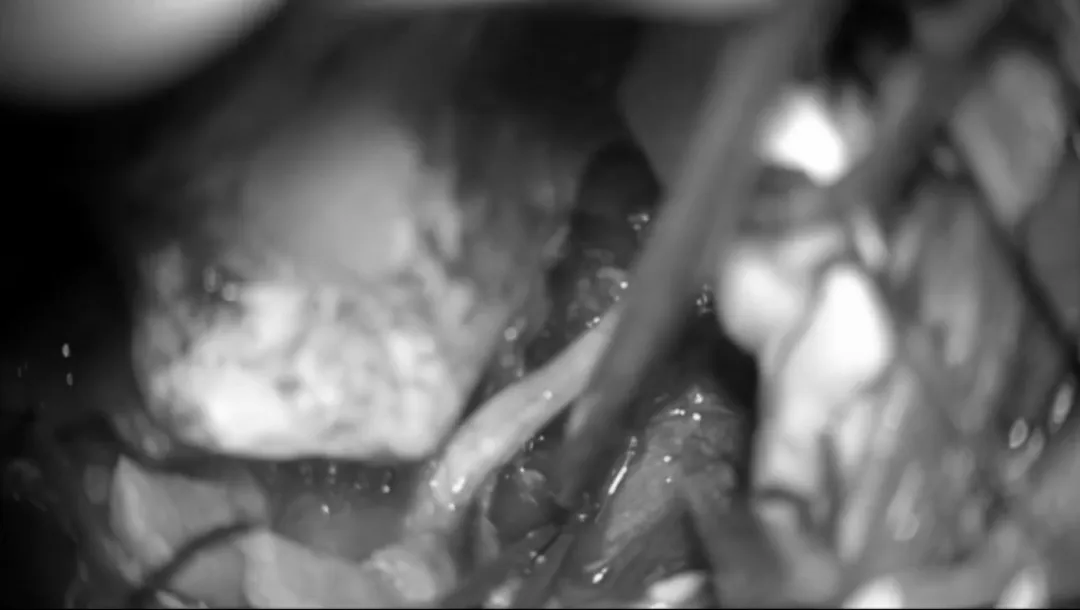

从肿瘤中分离、游离颅神经。使用显微镊来保留神经血管结构周围的蛛网膜平面。滑车神经在幕状韧带下方可见,使用CUSA刀进行逐步轻柔的肿瘤减压,这个操作对于保护位于这一重要区域的基底动脉穿支是非常重要的。

从病变中游离动脉穿支,在识别基底动脉后,使用低负压吸引器和显微剪逐渐移动肿瘤,将肿瘤从这些血管中分离揭牌。这种精细的操作是在高倍放大的显微镜下进行的,以便安全地分离蛛网膜和切断肿瘤的基底动脉及其穿支。

肿瘤的背侧表面也使用相同的技术进行解剖、分离。在脑干水肿和肿瘤紧密粘连于脑干的情况下,部分肿瘤残端需考虑保留,以避免损伤这些穿支。

第三对颅神经的识别。逐渐地,动眼神经被识别并从肿瘤中分离,同时沿着Dorello’s管方向分离解剖及保护外展神经。